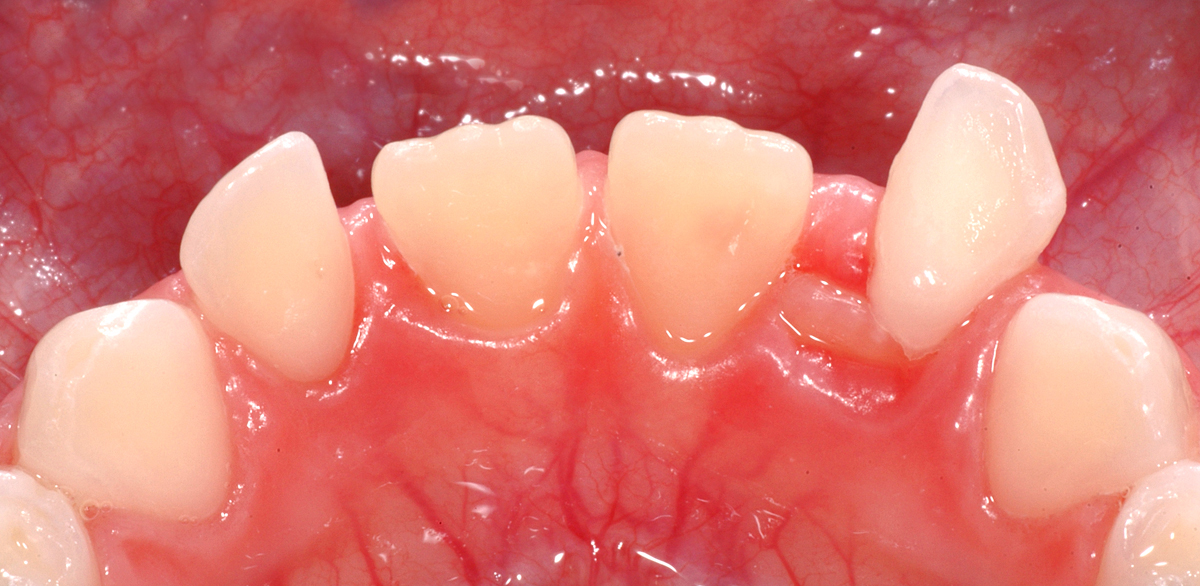

Anbei ein Fall einer knapp 6-jährigen Patientin, bei der der Zahn 42 (seitlicher Schneidezahn unten rechts) bereits durchbricht, der Milchzahn 82 aber noch vorhanden ist. Der Milchzahn ist schon sehr stark wacklig und wird demnächst aufallen. Wir nennen das «kurz vor Exfoliation».

Oft bereiten solche Situationen «Probleme», weil die scharfen Kanten, die durch das Auflösen der Zahnwurzel entstehen, bei Bewegung ins Zahnfleisch «stechen». Die scharfe Kante ist auf dem unteren Bild deutlich zu erkennen.

Diese Situation erfordert sehr selten eine zahnärztliche Intervention, hier ist eher die Zahnfee angesagt: an solchen Zähnen sollen die Patientinnen und Patienten einfach selbst ganz fest wackeln, bis die Zähne draussen sind. Damit ist dann auch das Problem der Schmerzen und des unangenehmen Gefühls behoben. Und wenn dann noch die Zahnfee was unters Kopfkissen legt, dann motiviert das vielleicht gleich für die kommenden Wackelzähne…